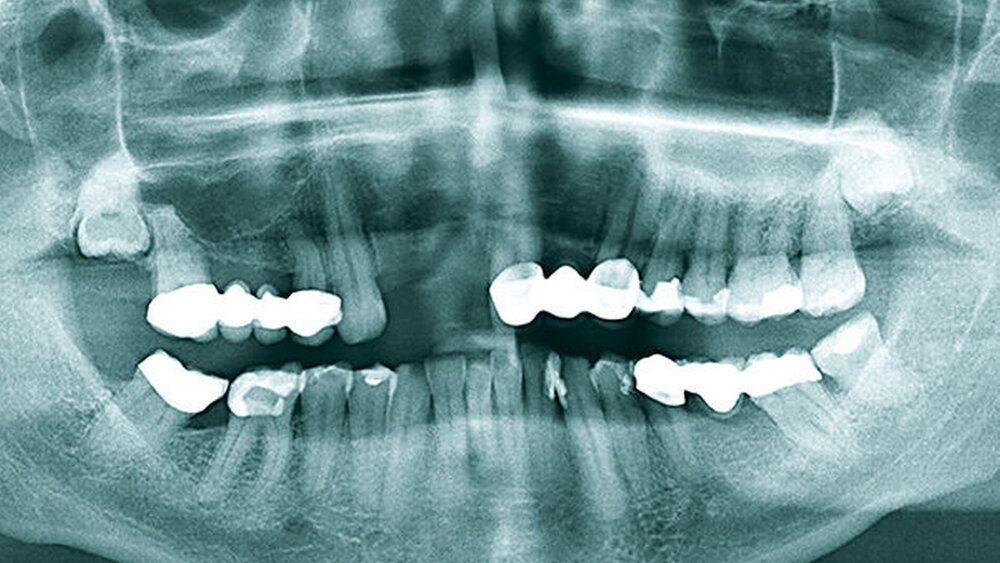

Als der 56-jährige Patient zu uns überwiesen wurde, waren die Zähne 11 und 12 bereits (alio loco) extrahiert (Abb. 2). Sie waren nach einer endodontischen Vorbehandlung mit begleitender WSR stark geschädigt und nicht mehr erhaltungswürdig (Abb. 1). Der Patient trug als Interimslösung eine herausnehmbare Valplast-Prothese. Er wünschte eine Implantattherapie. Eine konventionelle prothetische Lösung ohne Implantate war mit erhöhtem Aufwand verbunden, da der Patient bereits prothetisch mit einer festsitzenden Brücke von 21 bis 23 versorgt (Abb. 3) war. Diese hätte für eine konventionelle Lösung mit einer zirkulären Brücke von 23 auf 13 entfernt werden müssen. Das lehnte der Patient ebenso ab wie eine herausnehmbare Prothetik.

Nach Extraktion wurzelbehandelter Zähne liegt häufig ein horizontaler Kieferknochendefekt vor; die vestibuläre Knochenlamelle fehlt partiell oder vollständig. Das OPG (Abb. 3) zeigte genügend vertikales Knochenangebot, die lückenbegrenzenden Zähne und Parodontien waren vital. Die bidigitale Palpation bestätigte den Verdacht auf eine bestehende vestibuläre Defektgeometrie. Die chirurgischen Konzepte positiv unterstützend, lag ein dicker Gingiva-Biotyp vor. Der Restzahnbestand und parodontale Screening-Index (PSI) waren unauffällig.